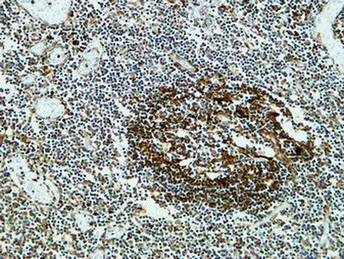

MPO Rabbit Polyclonal Antibody

Cat: APRab14056